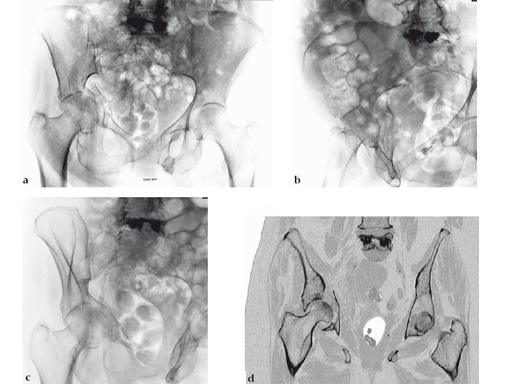

Fig 1ad AP pelvis, Judet oblique, and coronal CT scan views of associated anterior column plus posterior hemitransverse acetabular fracture. This pattern is problematic for multiple reasons, including mild impaction of virtually the entire weight-bearing surface with additional separate impaction of the displaced anterior column, quadrilateral surface comminution, and severe osteoporosis.